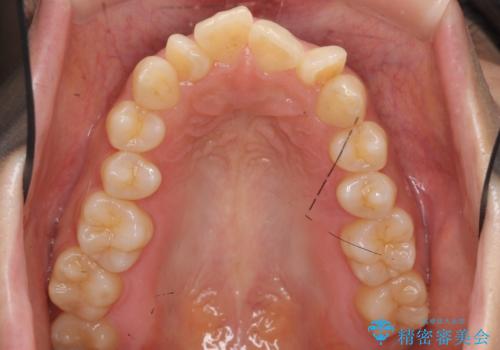

- 出っ歯を主訴に来院。

上下のかみ合わせが1本分左右ともずれていました。

①上下左右合計4本抜歯(口元は一番下がるプラン、上の奥歯をさらに後ろに下げる必要があるため②より時間がかかる、上下正中は合う)

②上の歯を2本抜歯、下の歯は前歯1本と最小限の抜歯(矯正治療は早く終わる、口元は下がる、抜歯は3本、上下の正中は合わない)

を提示し、

②を選択されました。